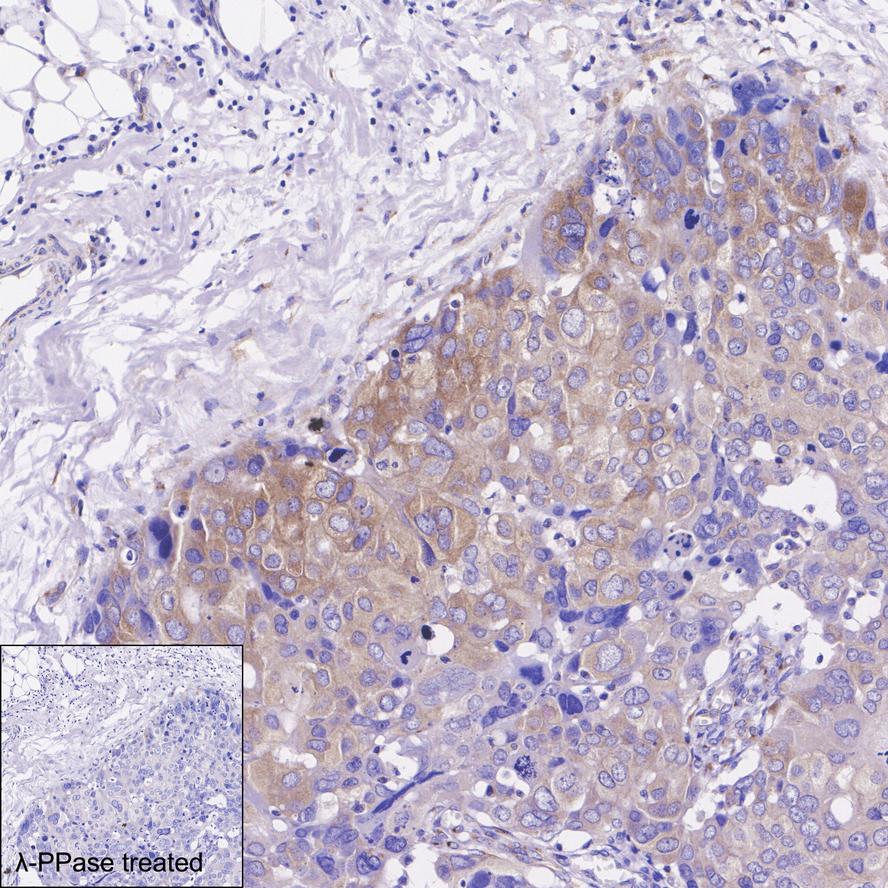

Phospho-eIF4G (S1108) Recombinant Rabbit Monoclonal Antibody [PS01-08]

IHC-P

Human